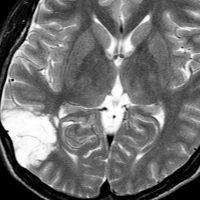

10代の少女に見つかったDNTです。難治性のてんかんがあり1日になんども意識減損を生じて,けいれんを止める薬をたくさん飲んでいて副作用のために眠気で日常生活が困難でした。でも,他の症状は何もありませんでした。左の頭頂葉と側頭葉と後頭葉の境目にできたものです。おそらくお母さんのお腹の中いたときからあった腫瘍なので何もしないで様子を見てもいいのです。でも,てんかん発作がひどいので腫瘍だけを摘出しました。DNTだけを取っても後遺症が残ることはほとんどありません。この場所は周囲の脳組織をとると後遺症がでる場所 (eroquent area)なので,てんかんを止める目的でもかなりの理由がないと周囲の脳組織は摘出しません。この子は,抗てんかん薬もいらなくなって完治しました。